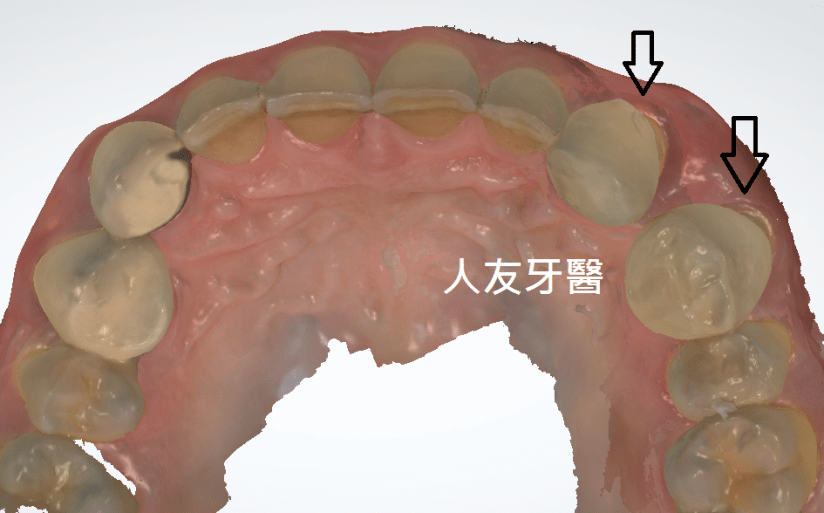

患者牙齒凌亂虎牙外暴大大影響外觀,並造成清潔不易、蛀牙、牙齦發炎等問題,透過醫師矯正評估分析建議矯正計畫內容包含拔牙、放置迷你螺絲(骨釘)等步驟,將原本凌亂外暴的虎牙歸位,改善咬合使發音更清晰,咀嚼效率更好,大幅改善清潔困擾,使日常刷牙及使用牙線清鬆有效率。

3.拔牙與骨釘:為騰出空間進行矯正,需要拔牙;骨釘用於輔助移動牙齒,初期可能會有異物感,但通常很快能適應。(下兩圖)

虎牙(犬齒)暴牙缺點(上左右2圖):

口腔清潔困難:虎牙暴牙形成清潔死角,易積聚牙菌斑和牙結石,增加蛀牙、牙周病風險。

影響咀嚼與咬合:犬齒主要功能是撕裂食物,位置不對會影響咬合功能,使食物難以充分咀嚼。

發音問題:虎牙暴牙可能影響舌頭的靈活性,導致發音不清晰。

口腔黏膜受傷:也可能經常摩擦或咬到嘴唇、臉頰內側,造成破皮或不適。

形成口呼吸:嘴巴不易閉合,容易養成口呼吸習慣,導致口臭、臉部肌肉鬆弛等問題。